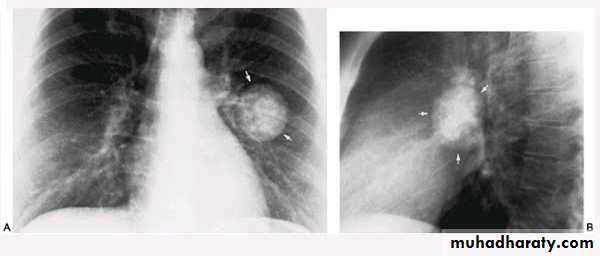

•Nodular (coin) lesion in the left upper lung with irregular edge (most probably cancinoma